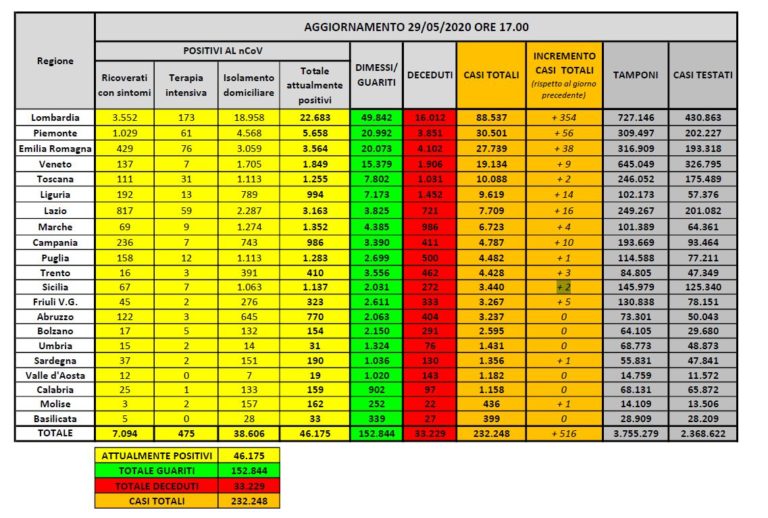

Al 29 maggio il totale delle persone che hanno contratto il virus è di 232.248, con un incremento rispetto al giorno precedente di 516 nuovi casi. Lo rende noto la Protezione Civile.

Il numero totale di attualmente positivi è di 46.175, con una decrescita di 1.811 assistiti rispetto al 28 maggio.

Tra gli attualmente positivi, 475 sono in cura presso le terapie intensive, con una decrescita di 14 pazienti rispetto al 28 maggio.

7.094 persone sono ricoverate con sintomi, con un decremento di 285 pazienti rispetto al 28 maggio.

38.606 persone, pari all’84% degli attualmente positivi, sono in isolamento senza sintomi o con sintomi lievi.

Rispetto al 28 maggio i deceduti sono 87 e portano il totale a 33.229. Il numero complessivo dei dimessi e guariti sale invece a 152.844, con un incremento di 2.240 persone rispetto al 28 maggio.

Nel dettaglio, i casi attualmente positivi sono 22.683 in Lombardia, 5.658 in Piemonte, 3.564 in Emilia-Romagna, 1.849 in Veneto, 1.255 in Toscana, 994 in Liguria, 3.163 nel Lazio, 1.352 nelle Marche*, 986 in Campania, 1.283 in Puglia, 410 nella Provincia autonoma di Trento, 1.137 in Sicilia, 323 in Friuli Venezia Giulia, 770 in Abruzzo, 154 nella Provincia autonoma di Bolzano, 31 in Umbria, 190 in Sardegna, 19 in Valle d’Aosta, 159 in Calabria, 162 in Molise e 33 in Basilicata.

La Regione Marche ha effettuato un ricalcolo del numero dei deceduti decurtandone 11 che non risultano classificabili come Covid-19.